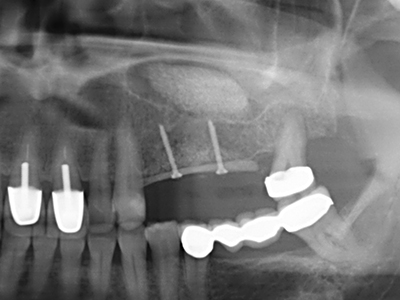

Sollen chirurgische Eingriffe mit unmittelbarer Knochenbeziehung an empfindlichen Strukturen wie Blutgefäßen oder Nerven erfolgen, so bergen rotierende Instrumente ein erhebliches Potential an iatrogener Schädigung. Gerade bei Nervdarstellungen nach iatrogener Schädigung, oder aber im Zuge einer Nervlateralisation für resektive und rekonstruktive Eingriffe oder Implantatinsertionen können piezoelektronische Geräte hilfreich sein Knochendeckel zu präparieren und nervnahe Hartgewebsanteile zu entfernen (Abb. 17-20). Ein leichter Kontakt des Nervstrangs zur Piezospitze bleibt dabei in der Regel folgenlos – allerdings kann eine unvorsichtige Vorgehensweise mit sägeartigen Bewegungen bzw. Ansätzen bei noch vorhandener knöcherner Unterlage durchaus temporäre oder aber auch permanente Nervschädigungen verursachen. Das Risiko einer solchen Schädigung wird jedoch als wesentliche geringer eingeschätzt als unter Anwendung von Säge- oder Fräsinstrumenten (Pereira, Gealh et al. 2014).

Wie sich in der Vergangenheit gezeigt hat stellt prinzipiell jeder knochenchirurgische Eingriff eine mögliche Indikation für die Piezochirurgie dar. So lässt sich die Präparation des mobilen Segmentes bei der Distraktionsosteogenese (Abb. 23-25) und der Sandwichosteotomie mit speziellen Ansätzen bewerkstelligen, ohne die für den Erfolg beider Techniken essenzielle Blutversorgung des krestalen Anteils zu gefährden (Gonzalez-Garcia, Diniz-Freitas et al. 2008).

Für die Entnahme von Implantaten ist die Präparation eines vestibulären Knochendeckels möglich, der nach Entfernung der Implantatschraube refixiert wird und auf diesem Wege die Kontur des Alveolarfortsatzes erhält.